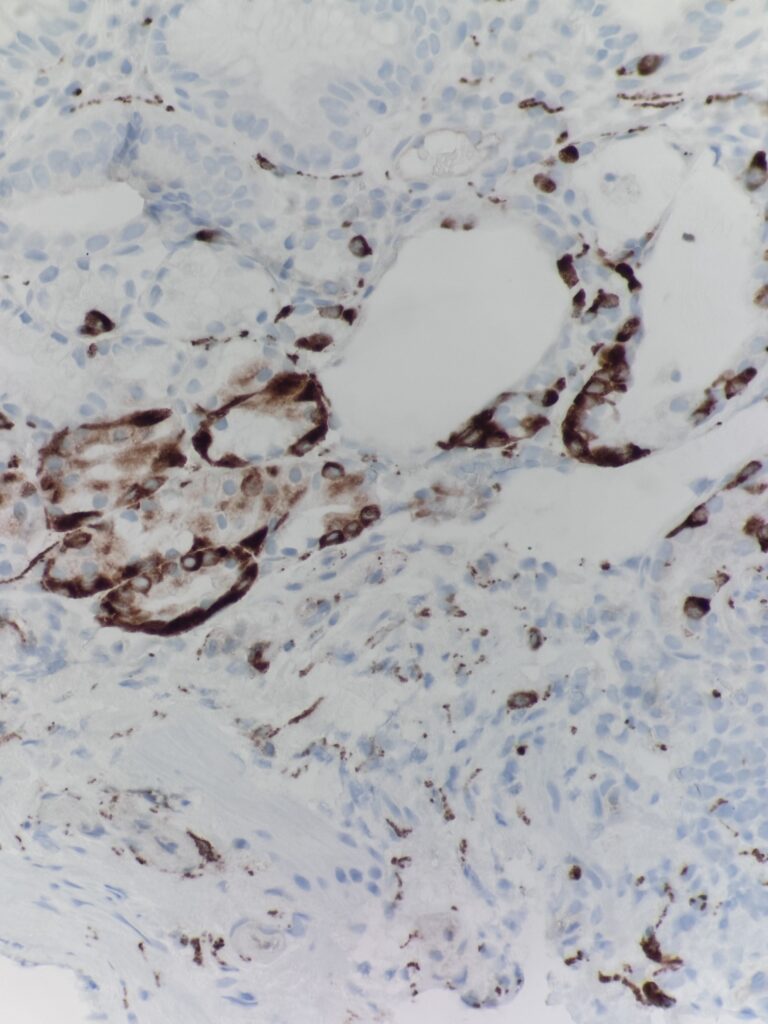

Diagnostic notes: As compared to H. pylori gastritis, the inflammation is predominantly in base of the mucosa extending to the superficial mucosa. There is loss of oxyntic glands, intestinal metaplasia, pancreatic acinar metaplasia and nodular and linear enterochromaffin like (ECL) cell hyperplasia. Gastrin stain can be used to differentiate antral vs. body mucosa – gastrin stain is positive in the antrum.